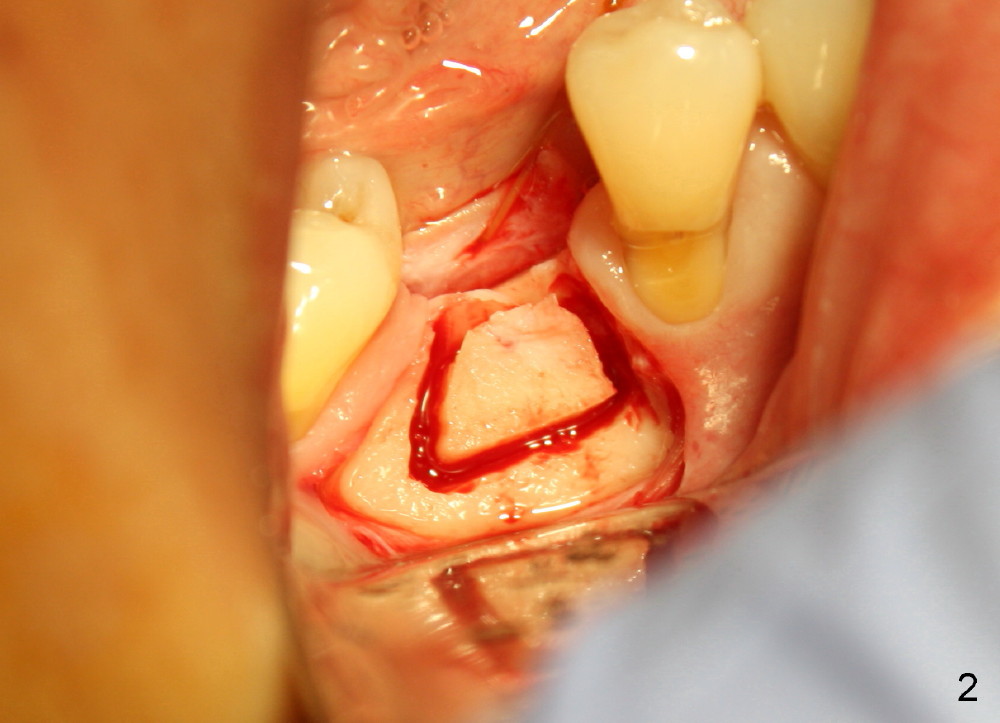

The ridge of the lower right molar is narrow buccolingually (Fig.1). After incision, ridge split is finished with a surgical fissure bur (Fig.2,3).

The patient is scheduled to return for implant placement 3 weeks later. The red lines in Fig.4 (CT coronal section) represent bony cuts in the ridge. A transverse incision is made over the top of the ridge with minimal exposure of the ridge. A curved osteotome is inserted into the upper bony cut (Fig.5). As the chisel is tapped in, the buccal segment moves buccally (Fig.6 pink arrow). When the chisel is withdrawn, a pilot drill is used to initiate osteotomy (Fig.7). As drills increase in diameter, the buccal segment continues moving buccally (Fig.8). Finally a bone-level implant (4.1 or 4.5x12 mm, Fig.9) or sub-crestal implant (4 or 4.5x8) is placed. Will the ridge split work?